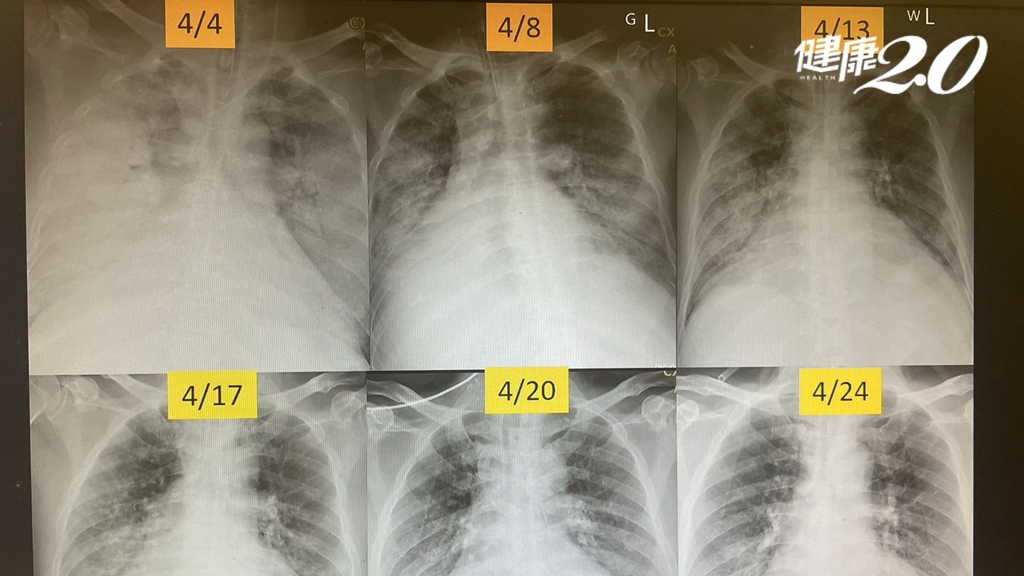

5旬男子血管炎肺全白了!一度急性呼吸窘迫險死 醫從鬼門關成功搶人

2023-08-29 14:56:00